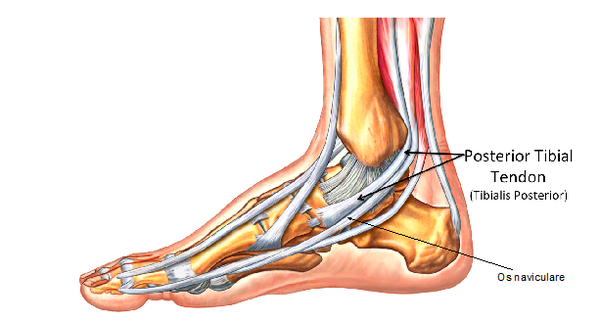

Mid Foot Pain Causes Symptoms Best Home Treatment

Treating the Flat Foot Chelsea and Westminster Hospital NHS Foundation Trust

Flat Feet Pain Treatment Hyperhealth